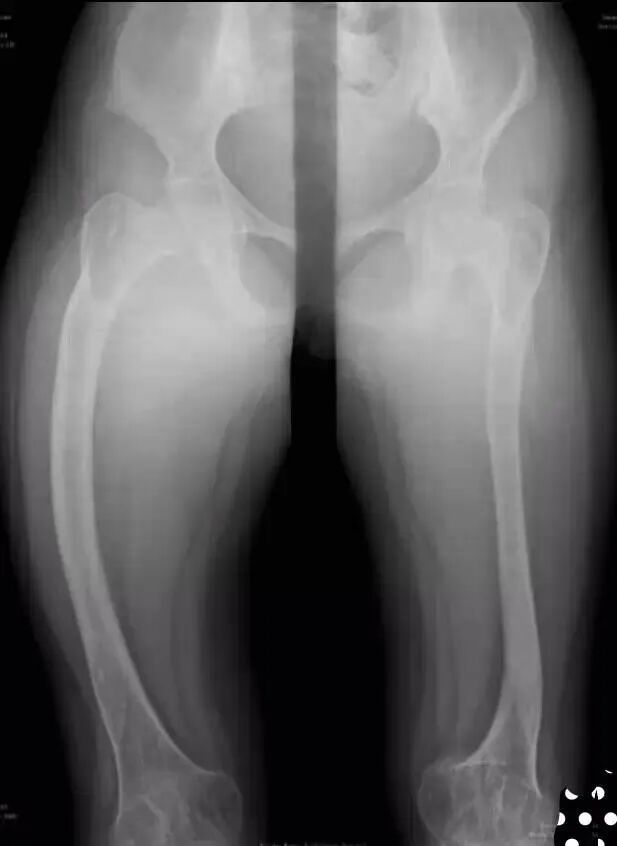

OI标志性特征是骨质脆弱反复骨折, 典型骨骼X线表现(见图二);成骨不全症的临床表现不仅限于骨骼,还常常累及其他结缔组织如眼、耳、皮肤、牙齿等(见图三)。根据临床表型, 澳洲悉尼大学的Sillence教授将OI 分成至Ⅰ-Ⅳ型[7]: Ⅰ型病情最轻, 最常见; Ⅱ最重, 通常围产期致死; Ⅲ型是存活者中最严重的, 常常身材矮小, 呈进行性骨骼畸形; Ⅳ型严重度介于Ⅰ型与Ⅲ型之间。近期发现的Ⅴ型OI 具有肥厚性骨痂、桡骨头脱位、前臂骨间膜钙化、桡骨干骺端下密集骺线等独特临床表现(见图四)。

1、在长骨表现为细长,骨小梁稀少,呈半透光状,皮质菲薄如铅笔画。髓腔相对变大,严重时可有囊性变。骨两端膨大呈杵状,可见有多处陈旧性或新鲜骨折。有的已经畸形连接,骨干弯曲。有一些畸形是因肌肉附着处牵拉所致,如髋内翻、股骨及胫骨呈弓形。某些病人在骨折后会形成丰富的球状骨痂,其数量之多,范围之广,使人会误诊其为骨肉瘤。另有一些病人的骨皮质较厚,称“厚骨型”。少见。